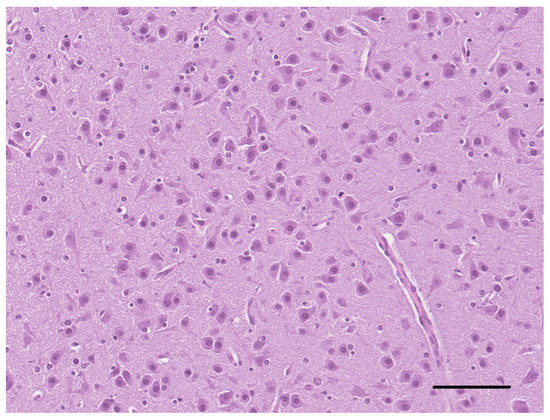

Three cases of the malformation of the cortical development are described: a mixed breed dog and a Border Collie pup with a focal and diffuse cortical dysplasia, respectively, and a kitten with lissencephaly. All cases presented with intractable epilepsy and were euthanized, due [...] Read more.

Three cases of the malformation of the cortical development are described: a mixed breed dog and a Border Collie pup with a focal and diffuse cortical dysplasia, respectively, and a kitten with lissencephaly. All cases presented with intractable epilepsy and were euthanized, due to the cluster of epileptic seizures. The gross examination at necropsy revealed the morphologic alteration of the telencephalic region in two cases. Histopathologically, a disorganization of the cortical lamination with the presence of megalic neurons, was found in the focal cortical dysplasia case. An altered organization of the white and gray matter, with a loss of the normal neuronal distribution and altered neurons, characterized the diffuse cortical dysplasia case. In the lissencephalic cat, there was no recognizable organization of the brain with areas of neuroglial tissue forming nodules in the leptomeningeal space. We strongly support the hypothesis that, as in humans, as well as in the veterinary patients, malformations of the cortical development could be the cause of refractory epilepsy. Full article